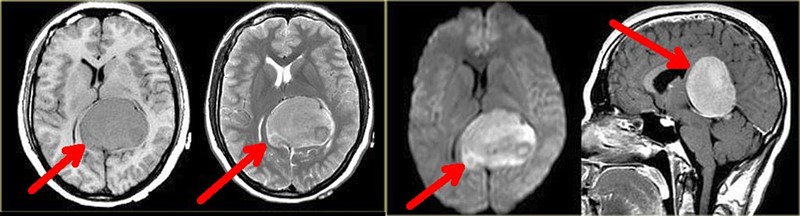

Na Sveučilištu u Pretoriji nalazi se prvi afrički Centar za tumore mozga i translacijsku neuroznanost (BTC@UP), u kojem timovi znanstvenika i neurokirurga testiraju metode kojima bi se preko oka mogli dijagnosticirati ozbiljni poremećaji u mozgu, uključujući i krvarenja i moždane tumore. S druge pak strane Indijskog oceana, u Australiji, istraživači iz Centra za istraživanje oka razvijaju sustave temeljene na umjetnoj inteligenciji koji bi mogli procjenom stanja krvnih žila mrežnice na očnoj pozadini procijeniti u kojoj mjeri imate ili nemate povišeni rizik za srčani ili moždani udar.

Znanstvenici u Pretoriji fokusirani su na moždane tumore i neurološke poremećaje. Triptih dijagnostičkih tehnika koje preporučuju su OUS + IRP + OCT, odnosno:

- ultrazvuk očne pozadine (ophthalmic ultrasound, OUS) - pretraga koja koristi ultrazvučne valove za prikaz unutrašnjosti oka, uključujući očni živac i krvne žile, a može pomoći u otkrivanju znakova povišenog tlaka unutar lubanje, jer se to može vidjeti kao oticanje (edem) očnog živca. Obavlja se prijenosnim uređajem s malenom sondom, a uz osnovnu edukaciju je lako osposobiti liječnike za obavljanje take pretrage.

- infracrvena pupilometrija (infrared pupilometry, IRP) se obavlja infracrvenom kamerom koja mjeri kako se zjenice (pupile) šire i sužavaju reagirajući na svjetlo, a promjene u tim reakcijama mogu upućivati na poremećaje u funkciji mozga, posebno u situacijama poput ozljede glave ili neuroloških bolesti. Vrlo je jednostavna, brza, objektivna i laka za uporabu, a potrebna obuka je minimalna jer većina uređaja je automatizirana, pa sâma bilježi i tumači podatke.

- optička koherentna tomografija (OCT) je poput "ultrazvuka sa svjetlom": koristi svjetlosne valove za stvaranje vrlo detaljnih slika slojeva mrežnice. Pomaže u otkrivanju promjena na vidnom živcu i mrežnici koje mogu biti povezane s bolestima mozga, poput tumora multiple ili skleroze. Trenutno su najveći nedostatci skupoća, složenost i osjetljivost OCT-uređaja, pa se kao „prva rezerva“ na terenu može koristiti alternativna metoda uvida u očnu pozadinu – fundus-kamera, koja snima digitalnu fotografiju očne pozadine, a postoji i u prijenosnim niskobudžetnim verzijama koje se montiraju na smartphone i moguće je očitavanje snimaka potpomognuto AI-algoritmima, čime se povećava pouzdanost pretrage.